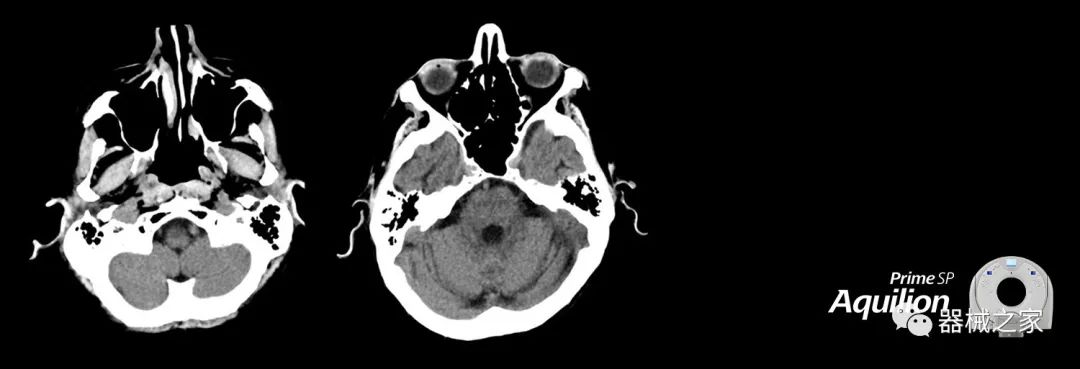

在以患者為中心的放射腫瘤學(xué)領(lǐng)域,計算機斷層掃描(CT)的可訪問性,可重復(fù)性和靈活性至關(guān)重要。為了建立這些價值,佳能醫(yī)療系統(tǒng)美國公司現(xiàn)在正在擴大其放射腫瘤學(xué)CT模擬產(chǎn)品,包括Aquilion Prime SP和Aquilion Lightning 80高級CT系統(tǒng)。除了Aquilion LB之外,Aquilion Prime SP和Aquilion Lightning 80現(xiàn)在還包括放射治療(RT)選項,可為腫瘤學(xué)規(guī)劃提供高質(zhì)量的CT成像和精密工具。

擴展視野(EFOV)可以看到更多的解剖結(jié)構(gòu)。Aquilion LB采用85 cm EFOV,而Aquilion Prime SP和Aquilion Lightning 70采用70 cm EFOV。

Aquilion Prime SP使設(shè)施能夠處理具有挑戰(zhàn)性的案例,同時為員工提供快速,靈活和高效的解決方案。

兩個CT系統(tǒng)均采用0.5 mm x 80排PUREViSION探測器技術(shù)(可配置并從80-160現(xiàn)場升級),78 cm孔徑,50 cm視野,AIDR(自適應(yīng)迭代劑量減少)3-D和SEMAR(單個)能量金屬神器減少)技術(shù)。

Aquilion LB專為滿足腫瘤學(xué)挑戰(zhàn)而設(shè)計,同時優(yōu)先考慮患者護理。Aquilion LB的內(nèi)徑為90 cm,能夠幫助復(fù)雜的患者設(shè)置并提高患者的舒適度。CT模擬定位可以輕松鏡像放射治療定位,更加自信。該系統(tǒng)采用0.5 mm x 16排(32層)PUREViSION探測器技術(shù),70 cm視野,AIDR 3D和SEMAR技術(shù)。